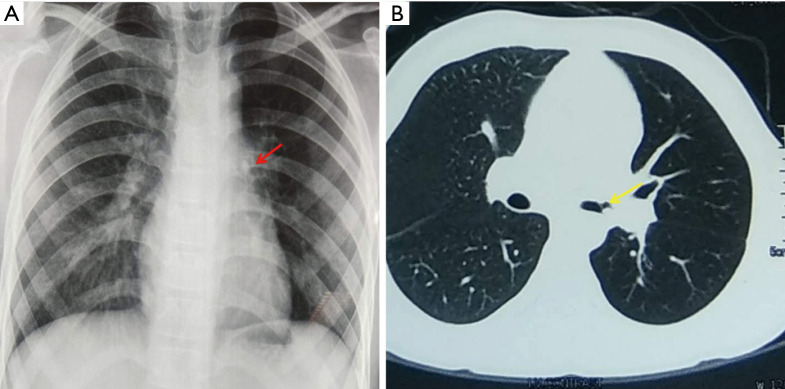

The initial diagnostic evaluation of patients with suspected FB aspiration includes obtaining a postero-anterior and lateral chest radiograph. The visibility of the aspirated FB depends on its radio-opacity, size, anatomical position in the airway and the patient’s body habitus. Organic foreign bodies like food particles and wood are generally radiolucent while inorganic ones like coins, stone particles, metals, glass pieces etc. are radiopaque. It is estimated that only around 26% of the aspirated FBs are radio-opaque and visible on chest radiographs (5). Indirect signs of FB aspiration seen on chest radiography include hyper-lucency suggesting air trapping (Figure 4), atelectasis, consolidation, and mediastinal shift. Blanco Ramos et al. reported the incidence of these radiological findings from various case series as: Consolidation (43%), atelectasis (15%) and bronchiectasis (5%) though absence of these does not exclude FB aspiration (5).

Figure 4.

A 13-year-old boy presented with history of whistling sound while breathing. A history of aspirating components of a plastic whistle 6 weeks back was elicited. (A) Chest X-ray demonstrates hyper-lucency of left lung with opacity (red arrow) in left hilar region. (B) Computed tomography showed a reverse C shaped artifact (yellow arrow) in left main bronchus with hyperinflation of left lung fields. A plastic whistle component was removed using sharktooth forceps that revealed significant granulation of the surrounding mucosa that was managed conservatively. Repeat bronchoscopy after 2 months showed normal lumen with mild inflammatory changes.